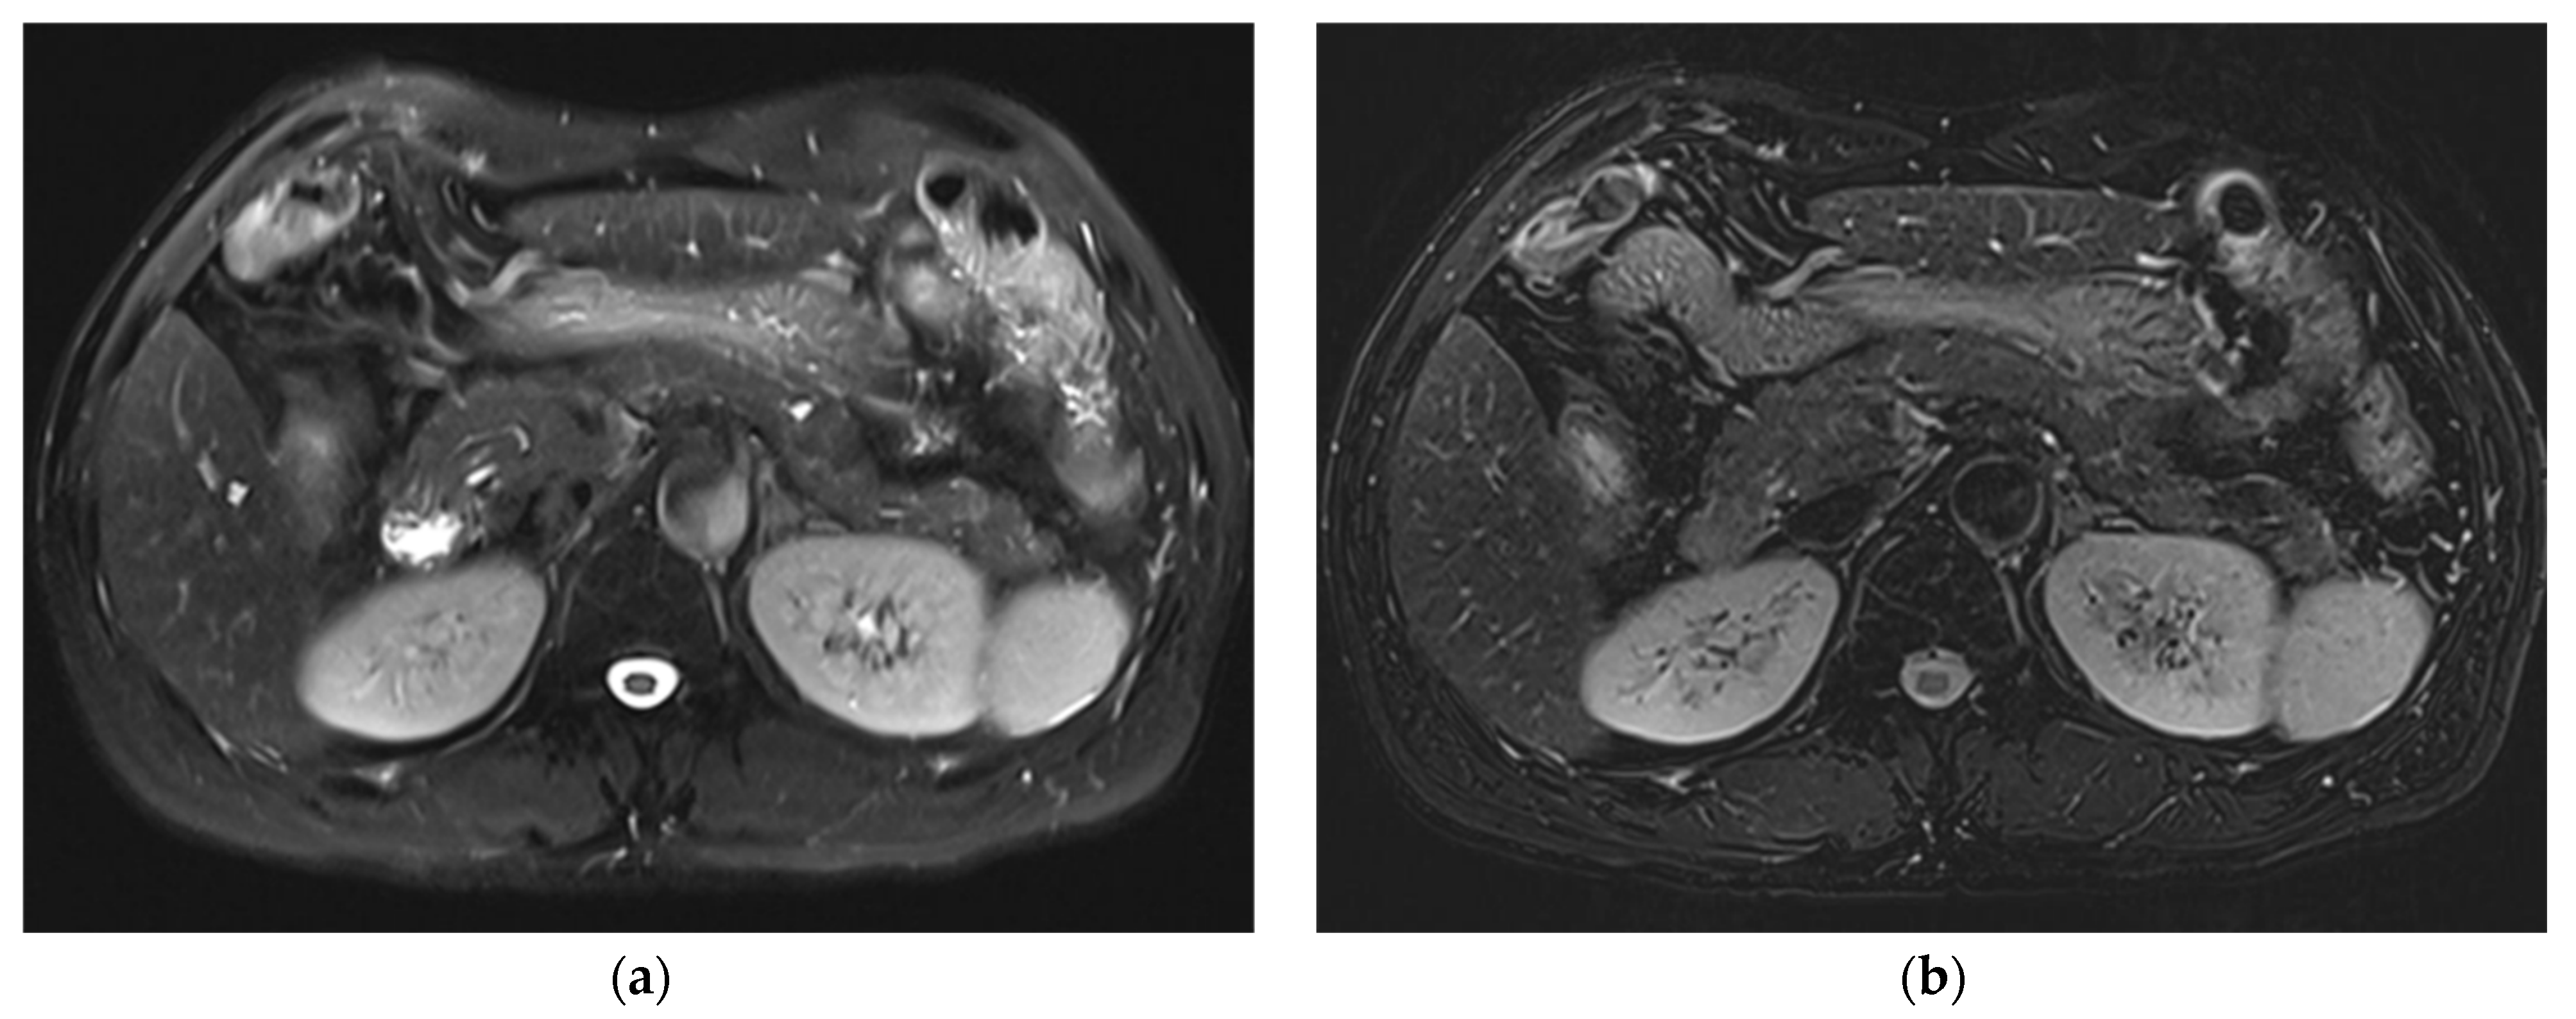

3.1. Subjective Image Quality

3.2. Lesion Assessment